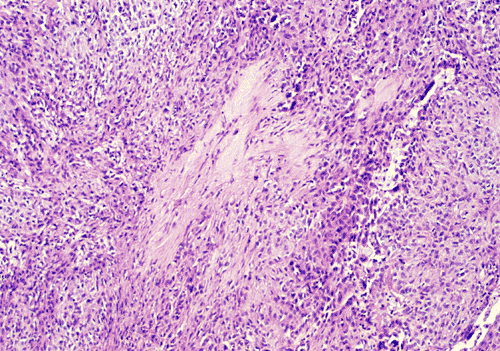

Panel A shows features of the periphery of the tumor that interfaces with the non-neoplastic lung parenchyma. Many choloesterol clefts are present and probably due to resolved hemorrhage. Panel B shows the periphery of the tumor which gives a papillary type of architecture although a real fibrovascular core is absent. Panel C shows the details of these areas. The lesional tissue appear to be composed of solid sheets of mononuclear cells with amphophilic cytoplasm. The cell border is quite clear in some areas but no intercellular bridges or keratinization is present. The surface of the solidly packed cells are lined by a single layer of cuboidal mononuclear cells. The papillary-like structures that are typically seen in the periphery transform into solidly packed tumor cells at the center of the lesion as illustrated in Panel D. Sclerotic changes is also present at the center of the lesion as illustrated in Panel E.

Microscopically, sclerosing hemangiomas have two salient histologic features: marked proliferation of sclerotic, small blood vessels and dual population of mononuclear cells with pale or eosinophilic cytoplasm and pnemocyte-like cuboidal cells. The interplay of these two components generates four recognizable patterns, namely, papillary, solid, hemorrhagic, and sclerotic.  The sclerotic pattern does not usually occur as a pure pattern but accompanies the three patterns. The center of the tumors tends to be more sclerotic. In the sclerotic areas, the collagen is dense and the tumor cells are sparse. In the papillary tumor, the periphery of the tumor has papillary structures lined by eosinophilic cuboidal cells that resemble the alveolar pneumocytes. These cells may continue with the surrounding non-neoplastic alveolar lining cells. There is often a transition of papillary pattern to broad areas of medium-sized, round or polygonal cells with pale eosinophilic or clear cytoplasm. The nuclei are usually oval, with fine chromatin and occasional nucleoli. The solid pattern is composed predominantly of solidly packed tumor cells without significant papillary component. The hemorrhagic pattern appears hemangioma-like and is associated with hemorrhage. A mixed pattern is seen in most sclerosing hemangiomas. Histologic changes secondary to the hemorrhage including hemosiderin-laden histiocytes, cholesterol clefts, and calcifications are common. Presence of tumorlets, areas with neuroendocrine features and foci of mucin production have been described as accompanying findings. The histological features are usually specific enough to allow rapid diagnosis.